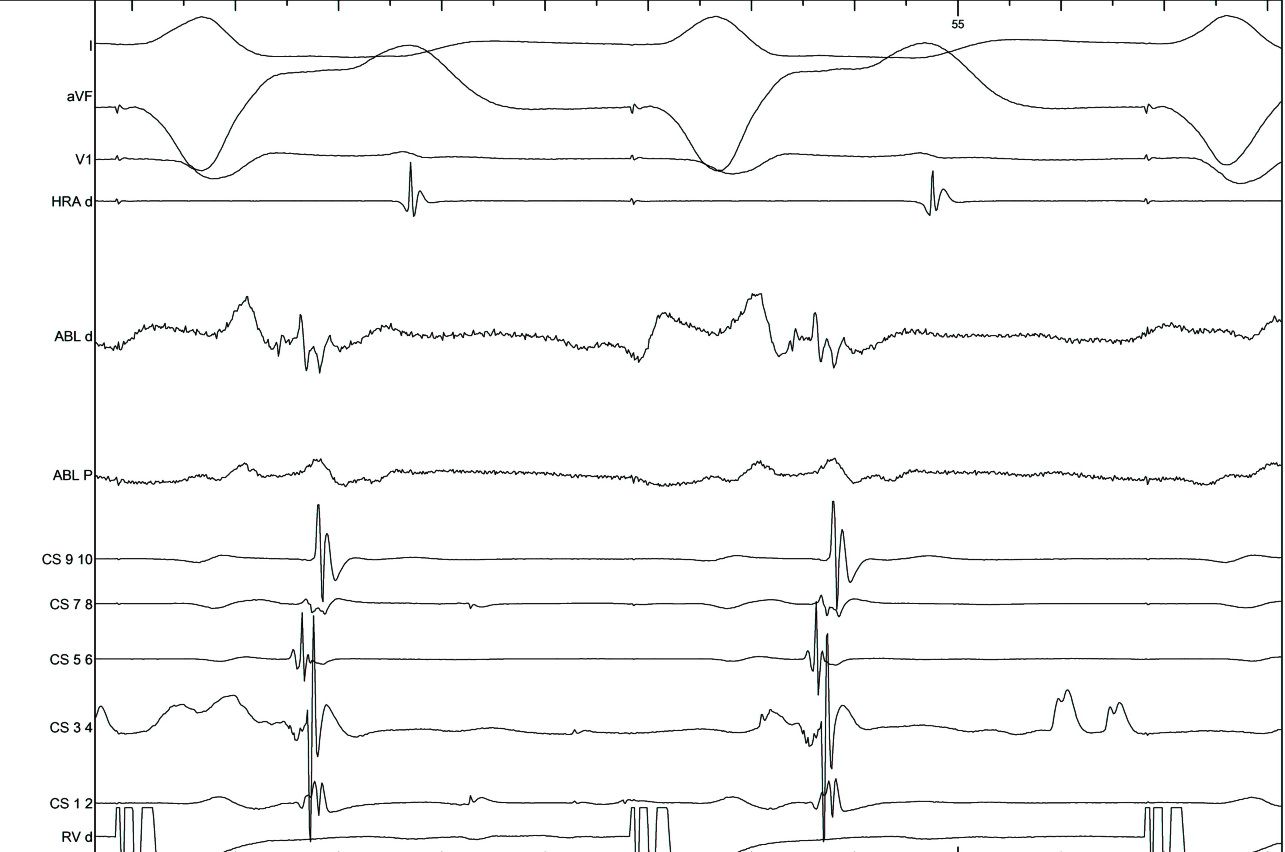

AP slant - Earliest A and earliest V may be distant

ap_med_lat1.jpg

ap_med_lat2.jpg

ap_med_lat3.jpg

AP slant - AP potential more important

pot_late_a.jpg